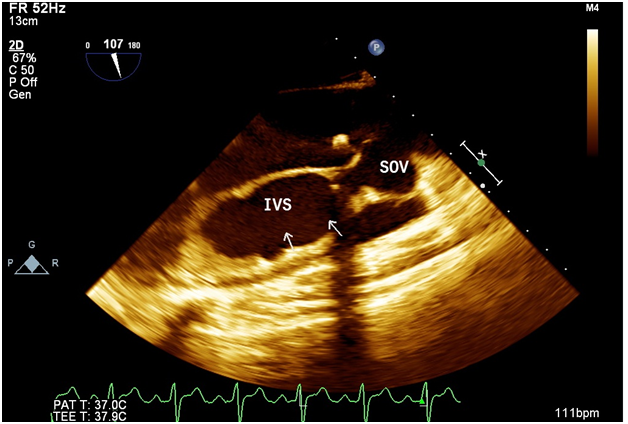

A 24 yrs old pleasant gentleman presented with history of gradually progressive shortness of breath and palpitation on exertion of 5 months duration. He also had history of 2 syncope 6 months prior. On examination he had wide pulse pressure with presence of peripheral aortic run off. Cardiac examination revealed displaced cardiac apex laterally with hyperdynamic apex beat, grade III early diastolic murmur over the aortic area. Rest of the examination was normal. Electrocardiogram revealed LBBB with first degree Atrio-Ventricular block with occasional ventricular premature beats. Chest X-Ray showed prominent bronchovascular markings. 2D echocardiogram revealed aneurysmal dilatation of right sinus of valsalva (SOV) which was burrowing and dissecting into interventricular septum (IVS) – echo free space as shown in Figure 1. LV was dilated with LVEDD of 5.4 cm and LVESD of 4.0 cm and reduced LV function (LVEF 40%). Aortic annulus was dilated (3 cm) and ascending aorta was of normal size. Aortic valve was tricuspid but deformed and calcified with evidence of severe aortic regurgitation. There was no communication of right sinus of Valsalva with any of the chambers. RA and RV were of normal size. TEE revealed same findings as in 2D echo, but both the right and left sinus of valsalva were seen dilated with the right coronary cusp (RCC) seen dissecting into the IVS with a nodular calcification in the vicinity of AoV as shown in Figure 2. Aortogram findings were also compatible with the 2D echo and TEE findings, which showed dilated right SOV without any evidence of leak into any of the chambers. Thereafter patient was taken up for aortic valve replacement along with repair and closure of the right sinus of valsalva aneurysm with Dacron patch. Intraoperatively there was a dilated right SOV with a cavity which led to the dissected IVS. The cavity was filled with calcium deposits and mural clots. The aortic side of the aneurysm was closed with Dacron patch, preserving the conduction system and avoiding the right coronary ostium. Post operative echo after 3 months showed completely healed and thrombosed aneurysmal sac of right SOV within the IVS as shown in Figure 3. There was no LV dilation (5 cms) with normal LV functions with normal functioning of the aortic prosthesis.

Figure 1: Aneurysmal dilatation of right Sinus of Valsalva (SOV) burrowing and dissecting into interventricular septum (IVS) – echo free space.